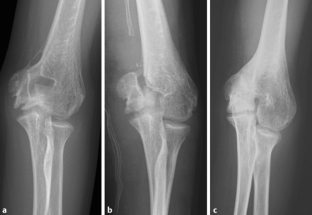

Es wird ein zum Unfallzeitpunkt 10-jähriger Junge mit Ellenbogengelenksluxation und Fraktur des Epicondylus medialis links präsentiert. Im Verlauf nach erfolgter medialer Kirschner-Draht-Osteosynthese wird eine Läsion des N. medianus beschrieben. Dass auch der N. ulnaris geschädigt ist, fällt erst mehr als 3 Jahre postoperativ auf. Daraufhin erfolgt eine operative Dekompression und Neurolyse des N. medianus und ulnaris, und es wird das Ergebnis 3½ Jahre postoperativ präsentiert.

We present the case of a 10-year-old boy with a dislocation of the elbow and fracture of the medial epicondyle. After closed reduction and K‑wire fixation from medial, he presents a median nerve palsy. That a lesion of the ulnar nerve is also present is only noticed 3½ years posttraumatically. A surgical decompression and neurolysis of the ulnar and median nerve is performed and the postoperative grip and key strength presented.

Abb. 1a–c